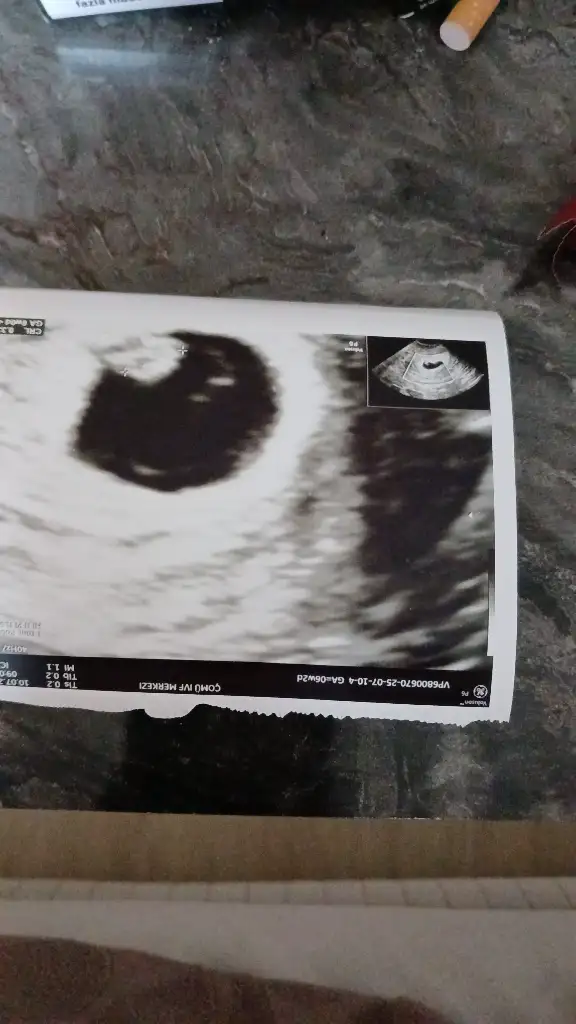

Hala hastanedeyim kanamam yok ama bebegin kalp atisi çok yavaş öyle bekliyoruz sabah akşam bakıyorlar hep ayni galiba durmasını bekliyolarMerhaba canım Nasıl oldun? Kanaman durdu inşallah çıktın mı hastaneden?

Çok geçmiş olsun bebişin sana sıkı sıkı tutunsun inşallahHala hastanedeyim kanamam yok ama bebegin kalp atisi çok yavaş öyle bekliyoruz sabah akşam bakıyorlar hep ayni galiba durmasını bekliyolar

Hala hastanedeyim bekliyorum kanama falan yok ama bebegin kalp atisi yavasCanım nasıl oldun

Insallah bugün 6+2 belki daha küçük olduğu için kalp atisi yavastir diye umutla bekliyorum 8. Haftaya kadar duymayan varmis inşallah düzelir dua edinÇok geçmiş olsun bebişin sana sıkı sıkı tutunsun inşallah

Ben oğlum da 8 de duymuştum mesela. Yani Dr o zamana randevu vermişdi erken olduğu için duyulmayabilir en garantisi 8.hafta demişti. İçini ferah tut herşey çok güzel olacak Allah'ın izniyle dualarımız seninleInsallah bugün 6+2 belki daha küçük olduğu için kalp atisi yavastir diye umutla bekliyorum 8. Haftaya kadar duymayan varmis inşallah düzelir dua edin

Evet benim doktorum 8 haftaya kadar bebeklerin kalp atışları yavaş olur demişti bu olağan bi durum şükür kiHala hastanedeyim bekliyorum kanama falan yok ama bebegin kalp atisi yavas

Ama bana pazarteside böyle yavaş olursa sonlandiracaz dedi doktorum bugünde dünle aynı kalp atisi yavas yine pazartesini beklicezEvet benim doktorum 8 haftaya kadar bebeklerin kalp atışları yavaş olur demişti bu olağan bi durum şükür ki

Evet 2 tane 5. Gün embriyosu biri tuttu ben iyiyim ama bebeğim iyi değil kalp atisi Hala yavaş pazartesi bakicaz dedi yine yavassa sonlandırıcaz çünkü bebek sağlıksız demekmisİyisin demi canım şuan ,? 5 gün embriyosu muydu

Aslında herseyi normalAma bana pazarteside böyle yavaş olursa sonlandiracaz dedi doktorum bugünde dünle aynı kalp atisi yavas yine pazartesini beklicez